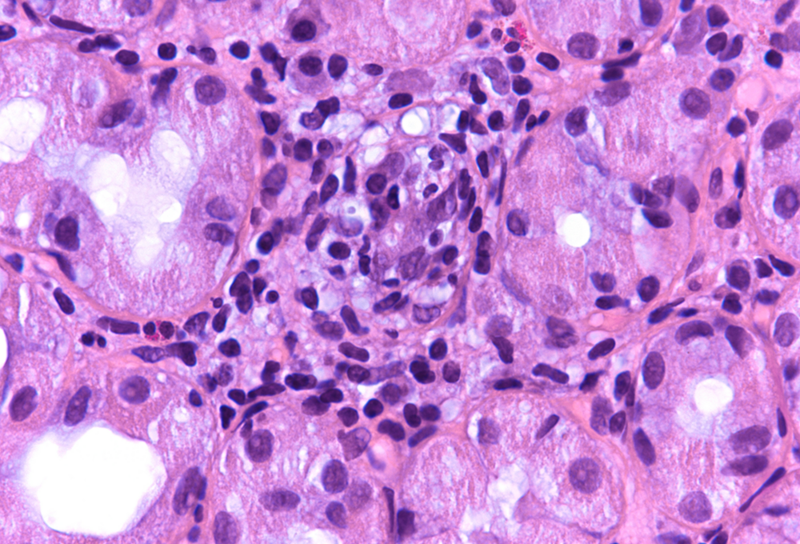

Microscopic examination revealed superficial chronic-active antrum and corpus gastritis (Panel A). In the mucus layer close to the surface epithelium, comma-shaped bacterial structures were detected and highlighted with a Warthin-Starry stain, consistent with Helicobacter pylori (Panel B). In the biopsies obtained from the corpus mucosa, a multifocal, predominantly lymphoplasmacytic infiltrate was seen in deeper parts of the mucosa. Specifically, the oxyntic glands were surrounded and infiltrated by lymphocytes (“emperipolesis”) resulting in gland destruction and parietal cell apoptosis. Occasional eosinophils completed the picture (Panels C-E). No significant atrophy and no metaplastic changes were observed.